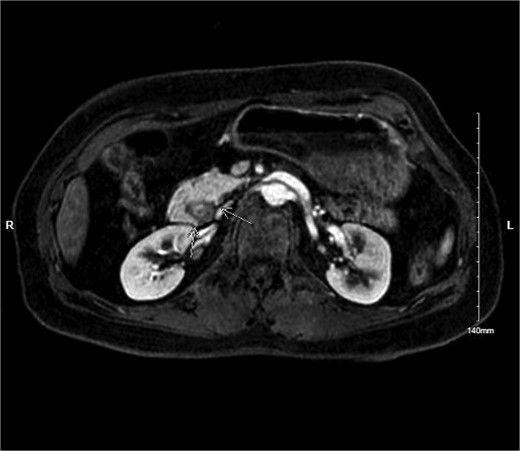

Physical exam was significant for epigastric and bilateral upper quadrant abdominal tenderness without guarding. Notably, her urinalysis was positive for ketones. Abdominal CT with intravenous contrast ordered in the emergency department revealed a near complete annular pancreas at the level of the first portion of the duodenum with concurrent gastric and duodenal bulb distension with no evidence of pancreatitis (See Fig. 1). Nasogastric tube decompression and antiemetic therapy were initiated, and the patient underwent magnetic resonance cholangiopancreatography (MRCP), which revealed severe duodenal narrowing at the second portion with circumferential encasement of the pancreas (See Fig. 2).

MRI MRCP showing annular pancreas causing near complete obstruction of the second portion of the duodenum.